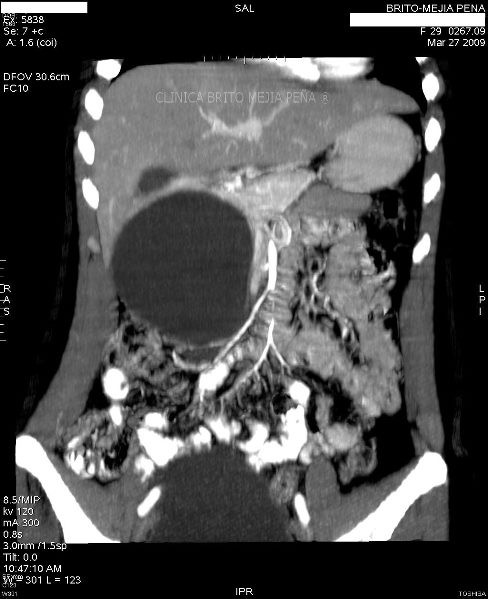

Pseudoquiste páncreas coronal